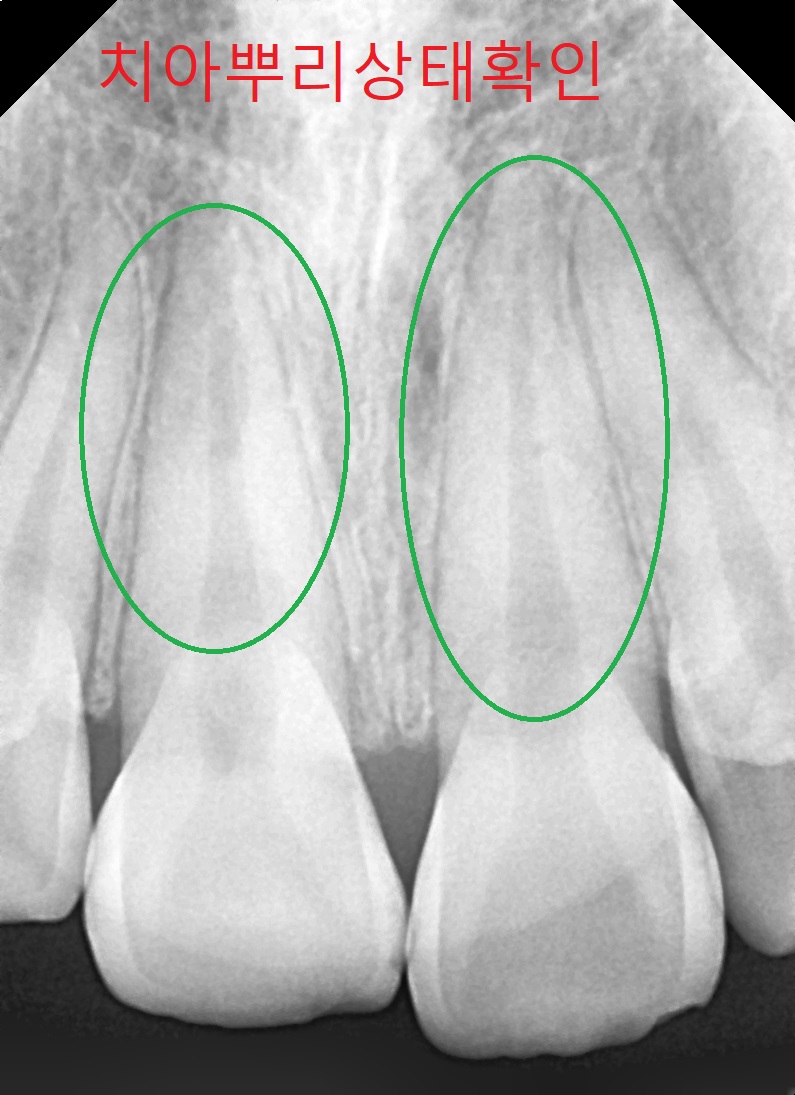

● 검사결과 내용

치아뿌리상태는 좋고 어금니 가위교합(3개월정도)을 먼저 하고 어느 정도 진행이 되면 전체브라켓을 설치 후 과개교합(2개월정도) 교정을 실시한후 2차 정밀검사를 하고 발치여부를 판단하기로 하였습니다.

▼ 1차 정밀 검사 X-RAY

▼ 치아상태 및 얼굴 각도 치아 치수확인